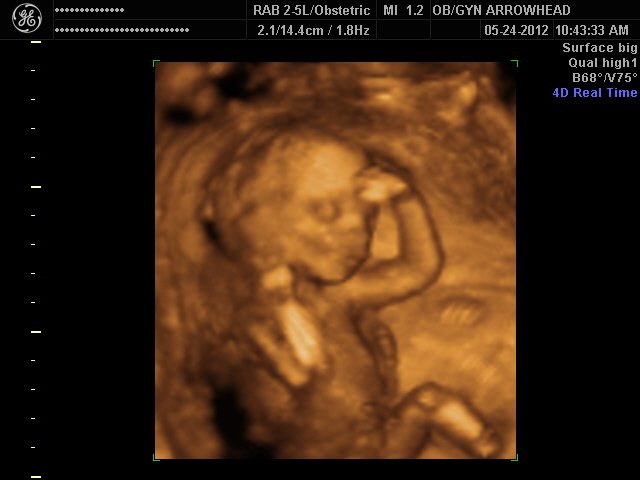

We offer complimentary 3D/4D Ultrasounds to all our OB patients around 30 weeks! The following photos are some examples of our work, shown with permission from our patients.